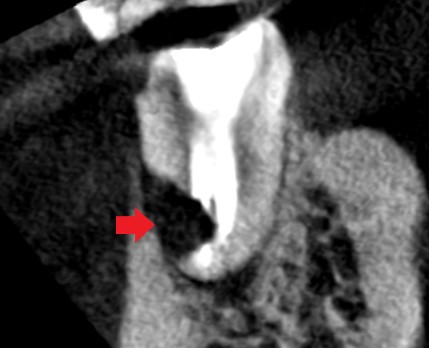

初診時の下顎第一大臼歯遠心根の冠状断のCT画像です。

赤い矢印の先に影がみられ、手術で斜めに根を切断した先の根が切りきれていないように見えます。

精密再根管治療1年後の下顎第一大臼歯遠心根の冠状断のCT画像です。赤い矢印の先に歯根膜ができ始めているようにみえます。